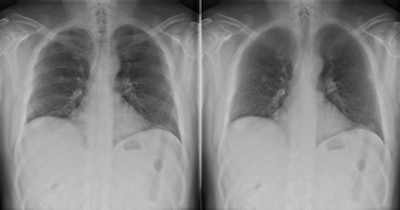

A 12-mm nodule in the right lung is completely obscured by overlying bone structures. The bone suppression software suppressed the ribs and improved the visibility of the nodule. All images courtesy of Dr. Steven Schalekamp.

A 12-mm nodule in the right lung is completely obscured by overlying bone structures. The bone suppression software suppressed the ribs and improved the visibility of the nodule. All images courtesy of Dr. Steven Schalekamp.In general, a chest x-ray is not taken to detect nodules, but they should be reported because solitary lung nodules, in the size range detectable by CXR, harbor a high risk to represent early stage lung cancer. A substantial number of bronchogenic tumors are missed on the initial radiograph, even though they are visible in retrospect, and the actual frequency of lung cancers missed on CXR ranges from 19% to 26%, according to Schalekamp and his colleagues.